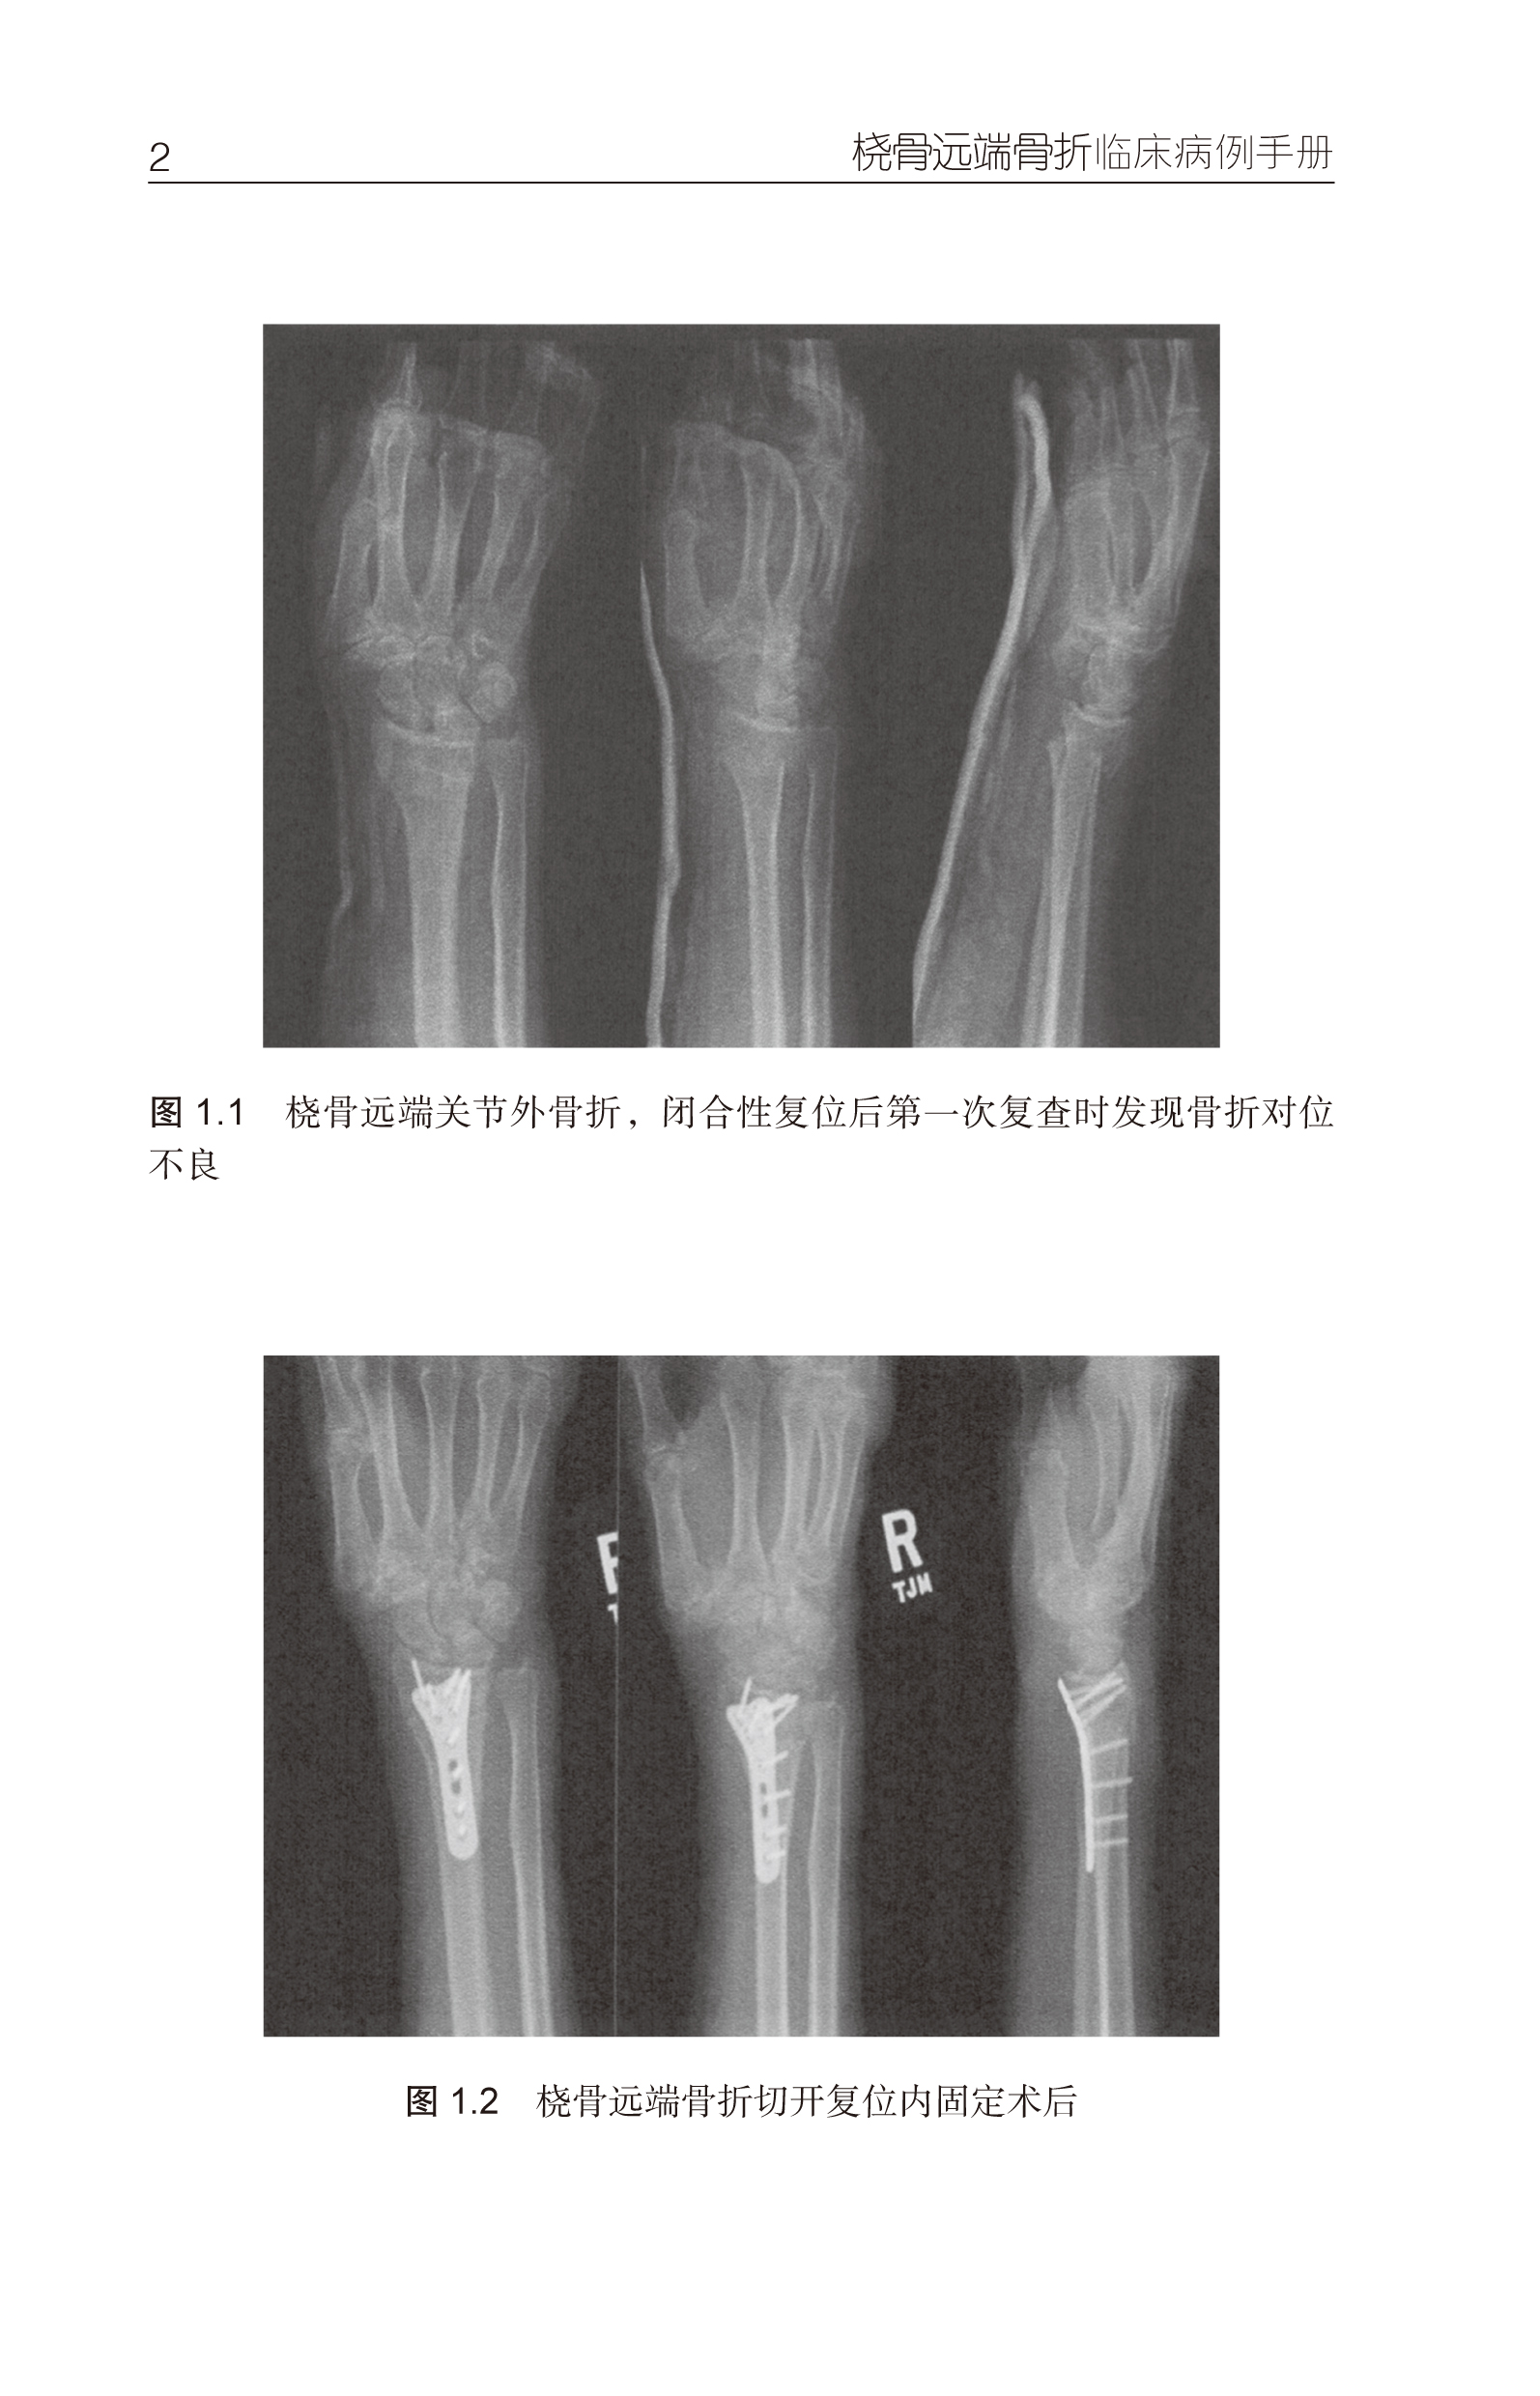

桡骨远端骨折是临床上常见骨折之一,在骨科急诊中有超过20% 的患者为桡骨远端骨折。本书主编Jeffrey N. Lawton 博士是美国密歇根大学手外科和整形科主任。他邀请全美多个手外科中心的骨科同仁,紧密结合具体临床病例,对桡骨远端骨折的经皮穿针复位内固定、外固定架技术、切开复位钢板内固定等主要手术治疗方法进行了深入浅出的讨论。对不同固定技术的适应证和手术技术在文献回顾的基础上进行了详尽的讨论和说明。作为实用手册,本书可成为住院医生的临床工作参考书,也可为经验丰富的骨科医生提供临床治疗决策的新思路。